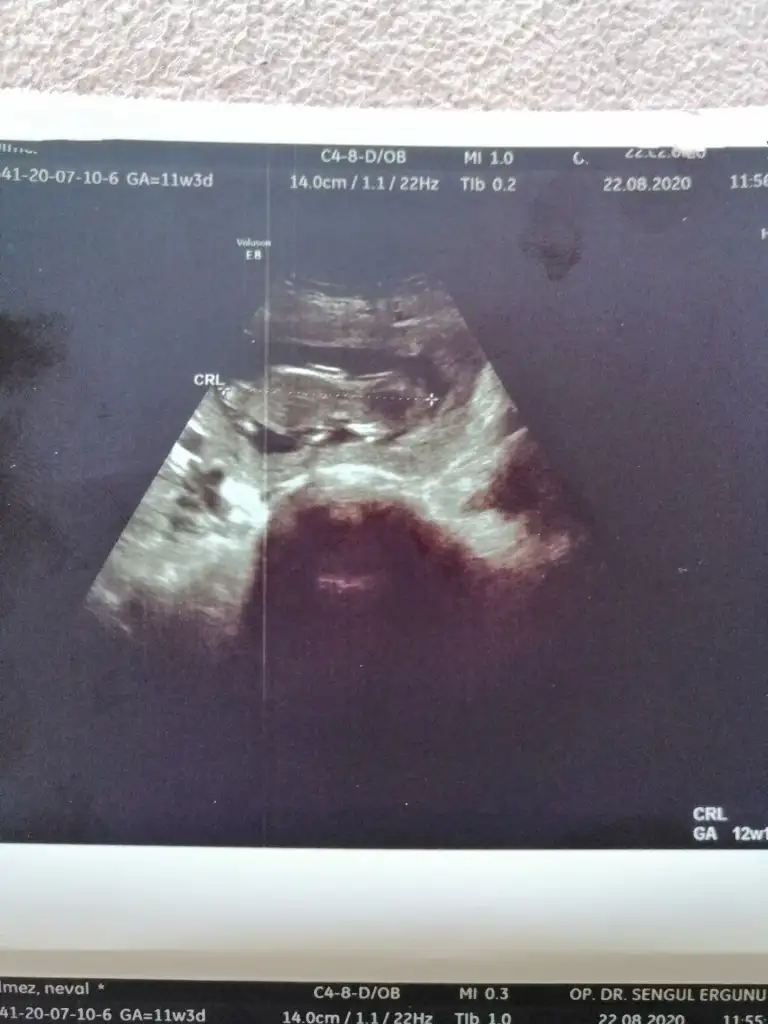

Eki Görüntüle 473831

simdi burada cikintilara bakin eger bel popo cizgisine paralel ise kiz

yok 30 derecelik bir aciyla yukari bakiyorsa erkek